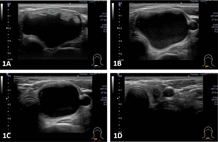

適合用於良性復發囊腫;但是對於很多良性實心甲狀腺結節就不適用。良性甲狀腺結節由於腫大且有壓迫感及美觀的困擾,傳統的手術或者是最新的內視鏡手術都可能會留下不美觀的疤痕,而超音波導引消融治療就提供一個無痕治療的選擇。醫師會使用消融針在超音波導引下,將腫瘤進行消融治療。消融治療適合4公分左右的良性甲狀腺結節,一般在半年後才能讓大小小於2公分,外觀便能達滿意的美觀。(圖二、超音波導引消融治療前後超音檢查圖片變化)

圖二、超音波導引消融治療成效(1A、消融前;1B、消融後一個月追蹤;1C、消融後三個月以上追蹤;1D、注射後半年以上追蹤)